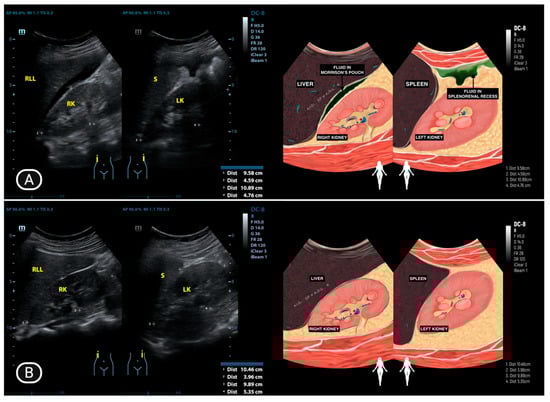

| 8 | OO (16) | Normal | Normal | Not visualized | Normal | Not visualized | Pocket Abscess | (−) |

| 9 | IHS (44) | Normal | Enlarged, cystic, unilocular, and contains simple fluid | Not visualized | Normal | Not visualized | Massive ascites | (−) |